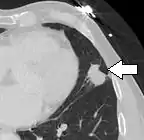

Nodule with pleural retraction.[9]

In this case, pleural retraction is seen as a triangular fat component.[9]